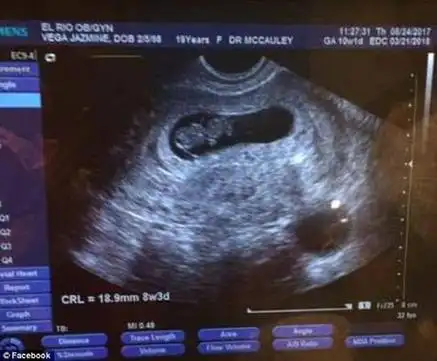

美国19岁孕妇睡梦中被枪杀 腹中胎儿幸存

高龄或有过流产史的孕妇需要做b超看胎心胎芽